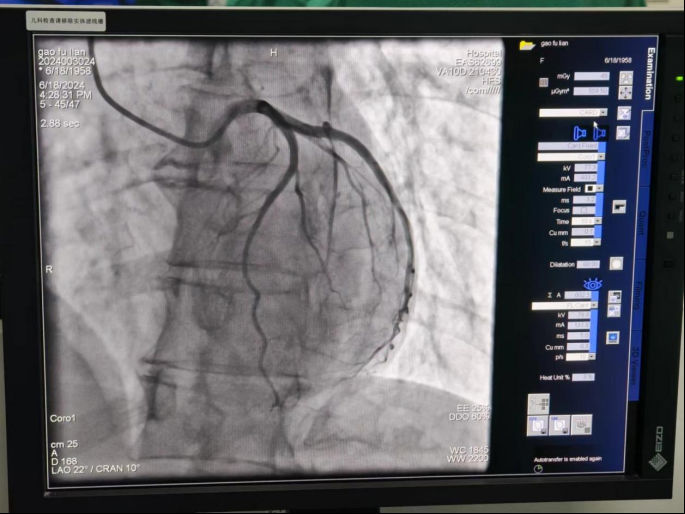

2024618日,甘肃省陇南市文县第二人民医院介入导管室正式启动。当天,在广元市第一人民医院心血管内科专家团队的帮扶指导下,文县二院成功开展2DSA经皮冠状动脉造影术),填补了该县在心血管介入领域的空白,标志着该县冠心病诊疗水平迈上了新的台阶,为当地广大冠心病患者带来了福音。

术前,广元市第一人民医院心胸血管内科三病区胡永奎副主任对两名疑似冠心病的患者进行了全面的评估和讨论,制定详细的手术方案手术过程中,胡永奎手把手指导基层医疗机构医护人员操作DSA设备,顺利开展两例DSA经皮冠状动脉造影术。

DSA经皮冠状动脉造影术是一种先进的诊断技术,通过向冠状动脉内注入造影剂,利用DSA设备捕捉血管影像,以明确冠状动脉是否存在狭窄或闭塞。此项技术的成功开展,基层医疗机构能够更加准确地诊断冠心病,为患者提供更为精准的治疗方案。